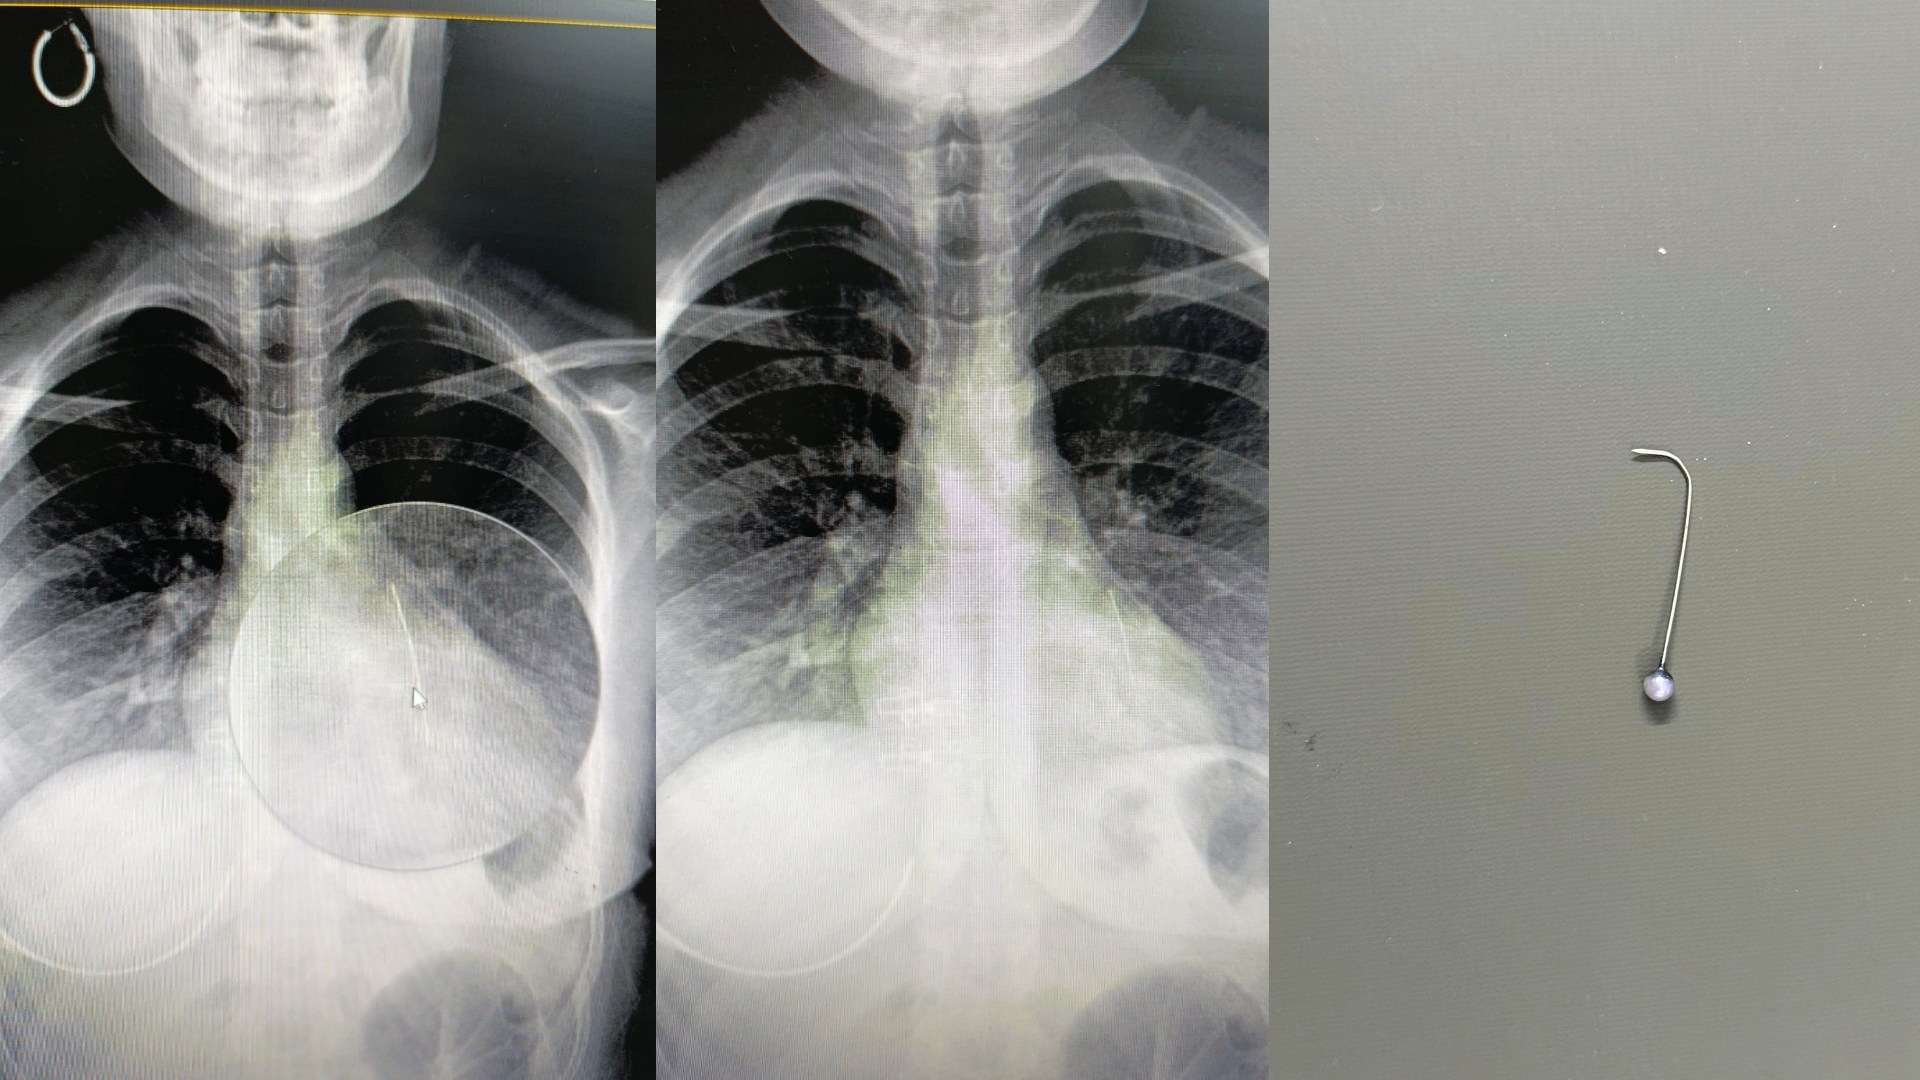

Olay, Günbalı Mahallesi’nde meydana geldi. Evden dışarı çıkmaya hazırlanan Bedia Özbay, eşarbını düzeltmek isterken ağzında tuttuğu toplu iğneyi yuttu. Nefes almakta zorlanan Özbay, ailesi tarafından Mehmet Akif İnan Eğitim ve Araştırma Hastanesi’ne götürüldü. Yapılan tetkiklerde iğnenin Özbay'ın sol akciğerine saplandığı tespit edildi. Hayati tehlikesi bulunan Bedia Özbay, Op. Dr. Mehmet Emin Balcıoğlu tarafından ameliyata alındı. Balcıoğlu, bronkoskopi yöntemiyle sol akciğerdeki iğneyi operasyonla çıkardı. Yaklaşık bir saat süren ameliyatın ardından Özbay’ın hayati tehlikeyi atlattığı belirtildi.‘BAŞARIYLA ÇIKARDIK’

Op. Dr. Balcıoğlu, operasyon sonrası yaptığı açıklamada, “16 yaşındaki hastamız, öğle saatlerinde başörtüsünü düzeltirken toplu iğneyi yutmuş. Öğlenden beri Şanlıurfa Devlet Hastanesi’nde bekliyormuş. Şanlıurfa ve çevre illerdeki hastaneler hastayı kabul etmemiş. Bronkoskopi yöntemiyle sol akciğerin alt kısmına yerleşmiş iğneyi çok şükür başarıyla çıkardık. Hastamızın durumu iyi, birkaç gün misafir ettikten sonra sağlıklı şekilde evine göndereceğiz” dedi.